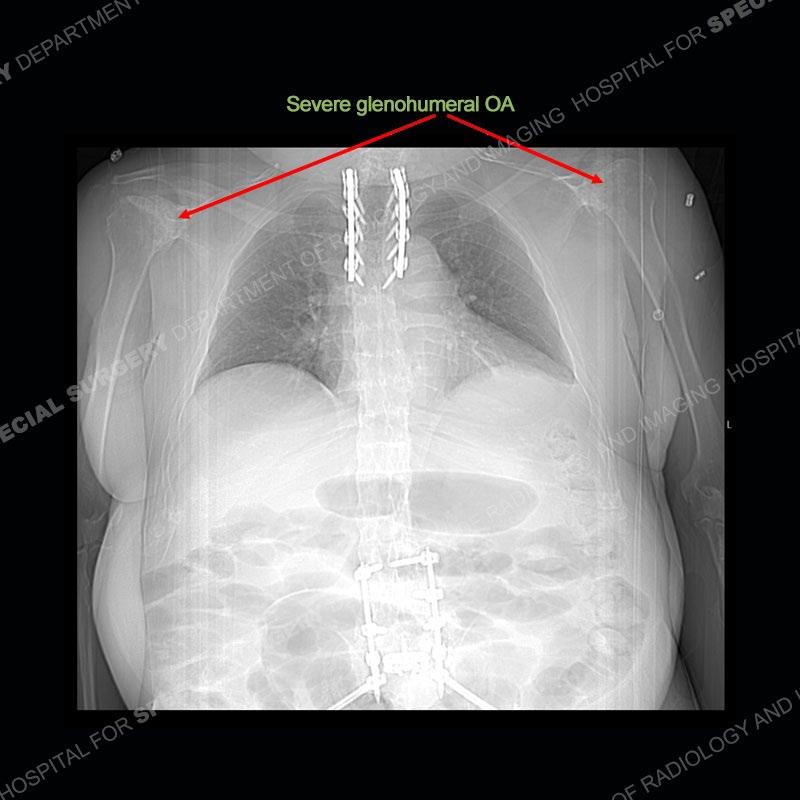

There is severe degenerative change of the left hip. The lumbar and thoracic spine show calcification of the intervertebral discs, loss of disc space, and bulky bony bridging across the disc spaces. Of important note is that the sacroiliac joints are open. They show advanced degenerative changes but not findings of an inflammatory arthritis. Bilateral knee arthroplasties are present and there are severe degenerative changes of both glenohumeral joints.

In comparison to ankylosing spondylitis (AS) where there are thin syndesmophytes of the outer annulus, this bony bridging tends to be bigger and bulkier. In addition, at this stage of AS the sacroiliac joints would be fused, but in ochronosis as seen here, the SI joints are open although with severe degenerative changes. No erosions are present of the SI joints, just advanced degenerative changes. This patient was treated with a left total hip arthroplasty and the black deposition of oxidized homogentistic acid of the cartilage is well shown.